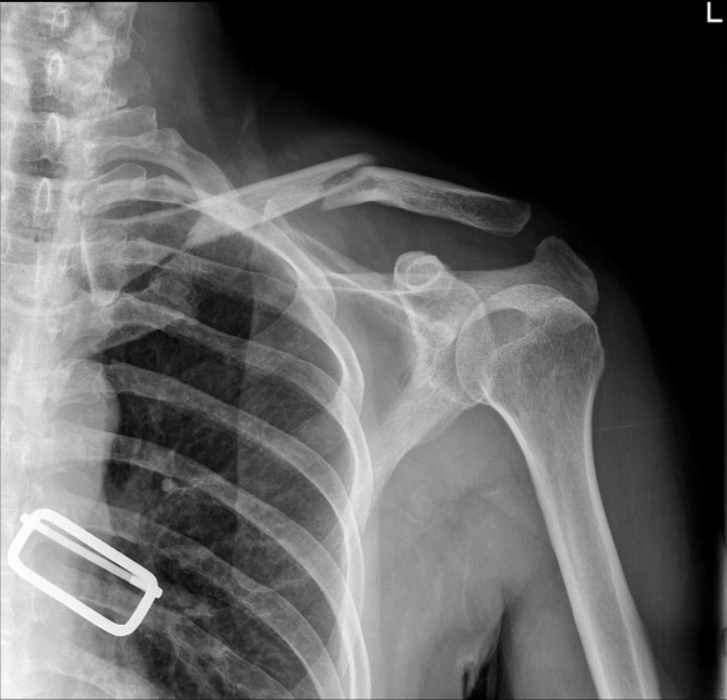

(A)在c臂图像增强器的帮助下,用克氏针将锁骨推入解剖位置进行闭合复位。(B)从肩峰尖端穿过肩锁关节(ACJ)至锁骨远端,用Knowles钉在锁骨远端后侧实现皮质锚定。采用Knowles销固定时,采用拉力螺钉技术保持ACJ空间。(C)术后x线片显示经皮Knowles针闭合复位治疗ACJ脱位复位良好。